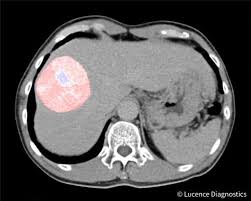

컴퓨터 단층촬영(CT) 스캔: CT 스캔은 간과 복부의 상세한 이미지를 제공하여 종양의 위치, 크기, 그리고 가능한 전이를 평가하는 데 도움이 될 수 있습니다.